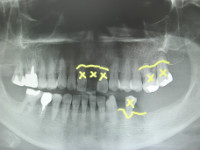

臼歯部、前歯部共にスプリットクレスト、GBRしての埋入でしたね。

この様な前歯部欠損の場合で臼歯部での垂直的な咬合が崩壊してしまっている場合は、まず臼歯部からの咬合の再構築を優先させなければいけません、前歯部歯牙は臼歯部でのしっかりとした垂直的な噛みあわせがあるからこそ守られているという事を認識しておく必要がありますね。!